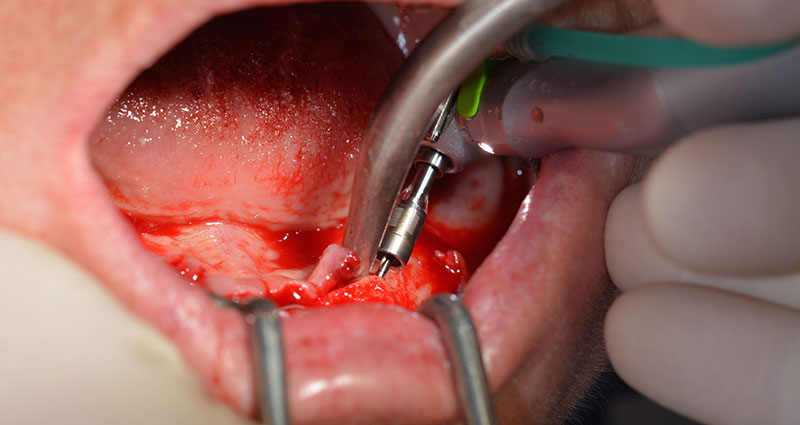

Le prochain réglage programmé est destiné à la mise en place des implants. Dans notre cabinet, nous appliquons généralement un couple de 32 Ncm pour cette phase (Fig. 12 et 13).

Une grande stabilité primaire est une exigence essentielle à la restauration immédiate. Pour s'en assurer, le forage n'a pas été taraudé ici. L'unit de chirurgie Implantmed W&H utilisé ici est doté d'un mode spécial adapté qui peut être directement sélectionné et est indispensable à de nombreuses indications. Lors du positionnement des implants, les derniers tours ont été effectués avec une valeur supérieure à 32 Ncm et ont été effectués à la clef à cliquet. Dans un tel cas, nous recommandons d'utiliser la fonction d'auto -taraudage de l'implant et de tourner plusieurs fois les implants vers l'arrière et vers l'avant.

Ceci permet à l'implant de s'approcher de la position finale progressivement sans exercer de pression excessive sur l'os (Fig. 14).